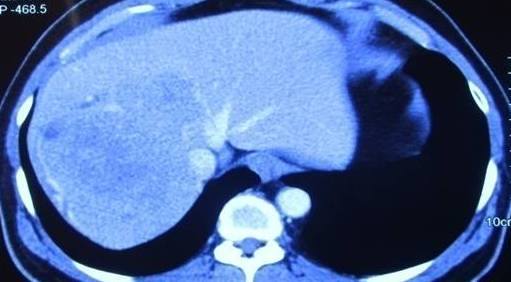

Child’s A CLD with HUGE gastric varices uncontrolled by Endoscopic glue and attempted EUS coiling. One salvage option would be TIPSS with balloon vascular occlusion but due to logistics we went for modified sugiura procedure. Splenectomy + Gastro esophageal devascularisation with anterior Gastrotomy and overseeing of gastric varices with pyloroplasty. Images show 1 CECT showing large gastric fundal varices. 2,3,4 Gastro Esophageal devasc 5, 6 Large fundal varices before and after oversewing. 7. Anterior gastrotomy 8. Pyloroplasty. Postoperative recovery was uneventful.